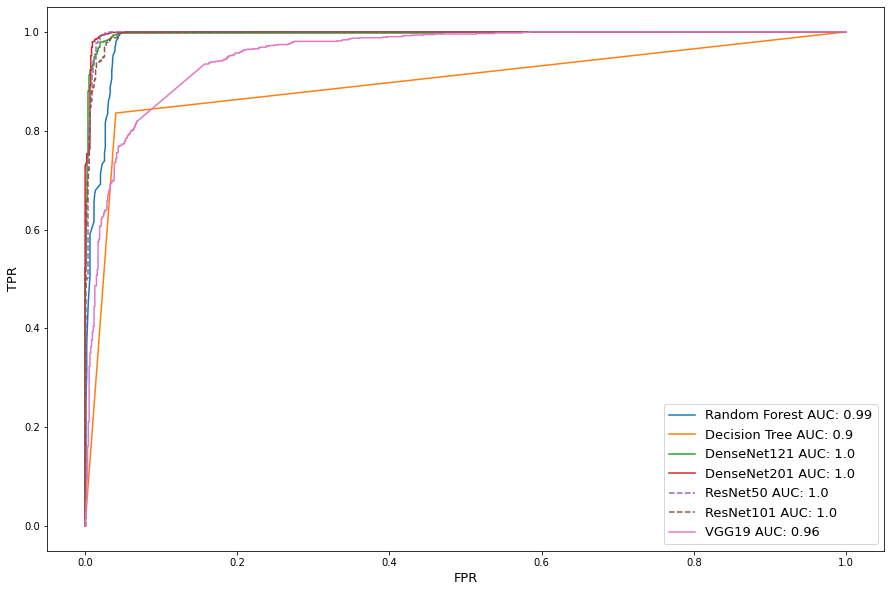

The eight models are trained without data preprocessing on all tampered images, and a subset of untampered images to balance data quantity for classes. Table 2 shows train and test performance metrics for the classifiers. The SVM, Random forest and Decision tree perform much better then deep learning models. Insufficient data severely hindered deep learning models’ accuracy due to overfiting issue. Figure 2 shows the receiver operator characteristic (ROC) curves, where TPR and FPR represent true positive rate and false positive rate respectively. The ROC curve is created by plotting the TPR against the FPR at various threshold settings, which is a commonly used plot to qualify the diagnostic ability of a classifier. The area under the curve (AUC) summarizes the quality of classification and is used as another measure of accuracy, where an AUC of 0.5 indicates a random classifier with no predictive credibility. The results show ResNet101 is able to reach 80% TPR with the hindrance of a 50% FPR rate and would be considered poor (El Khouli et al., (2009)). FPR addresses classification accuracy of tampered scans and is required to be minimized as much as possible in order to avoid life threatening misclassification. Given low quantity and high dimensional data, the bootstrap aggregation and random feature selection allow the random forest to produce a high performance. However with limited test sample presence, further testing is required to determine true accuracy levels with features at scale.

Table 4 shows the classification performance for the augmented data. We see the addition of data allows near perfect score improvement for the deep learning models. However, the increase in sample size decreased overall conventional machine learning algorithm accuracy due to a higher possibility for false predictions. This phenomenon is also reflected in Figure 6 as deep learning reached AUC scores nearing 1.0, while the Decision Tree AUC score dropped 0.05 from Figure 5.